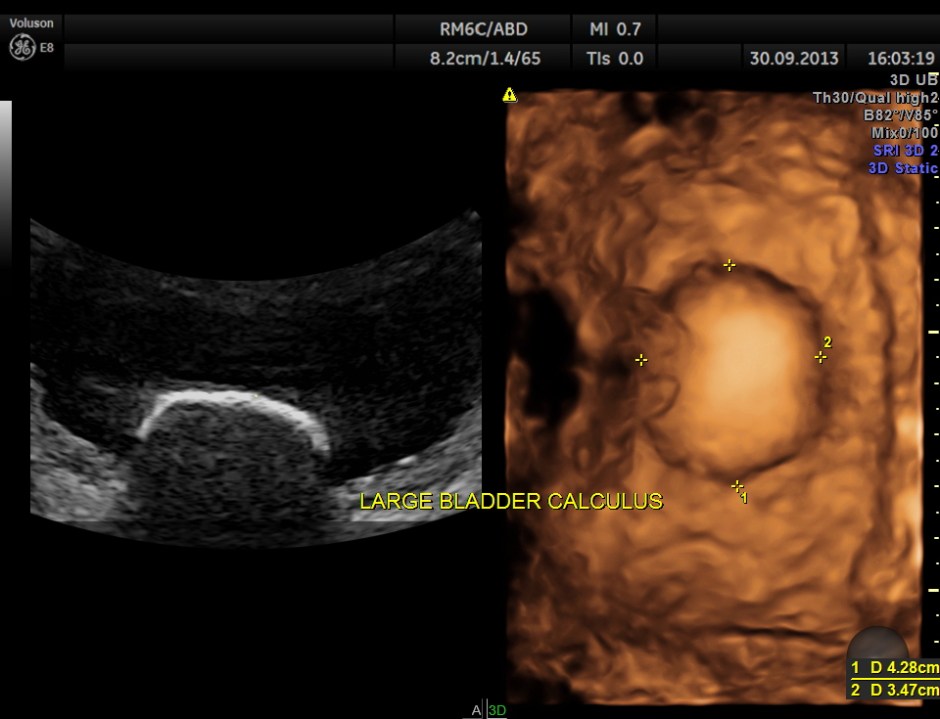

urinary bladder showed a large calculus and prominent swelling of the median lobe of the prostate.

2 D and 3 D of the bladder calculus alone.

The diagnosis given was Large calculus in the urinary bladder , Severe prostatic enlargement with prominent median lobe hypertrophy , causing Right sided obstructive uropathy.

The diagnosis was made with the 2D images , but the 3 D images were very helpful in explaining to the patient.